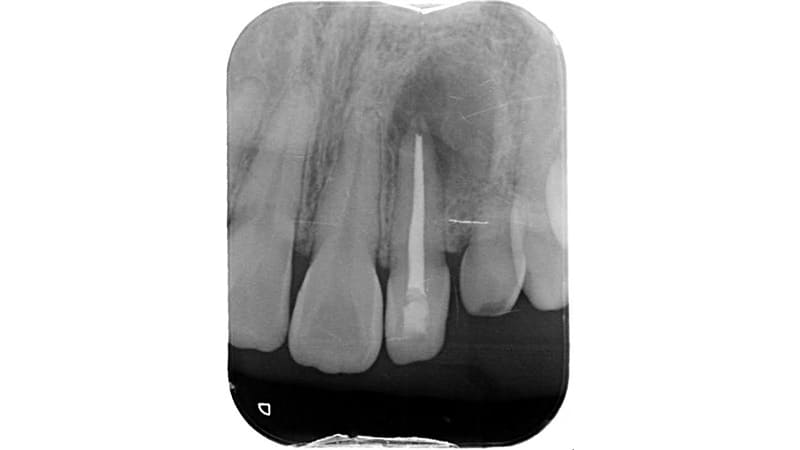

症例①:他院で根管治療していたが膿が止まらないと言われた

| 治療科目 | 根管治療 |

|---|---|

| 主訴 | 他院で根管治療していたが膿が止まらないと言われた。 |

| 治療期間 | 1ヶ月 |

| 治療費 | – |

| 治療内容 | 前歯、根管内をマイクロスコープで確認し汚染部位を除去し根充。 |

| 治療のリスク | 噛み合わせが強い場合歯根破折の可能性あります。まれに再発する可能性があります。その場合外科的歯内治療をするか、抜歯を検討します |